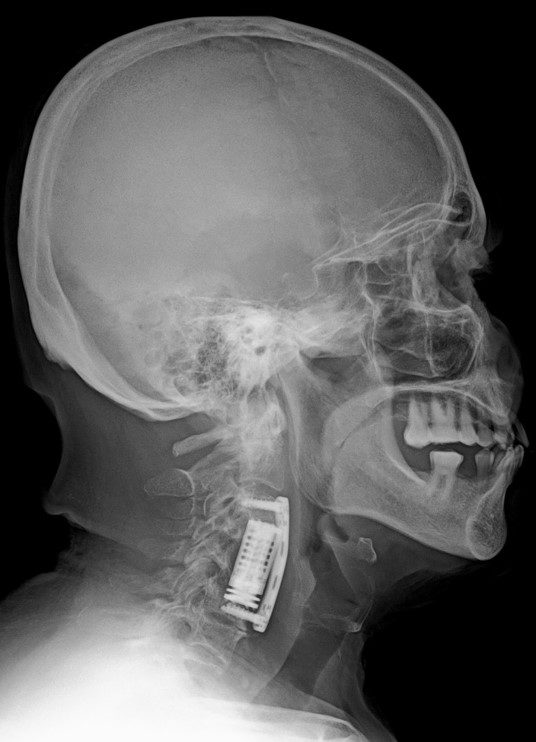

Ameliyat Sonrası